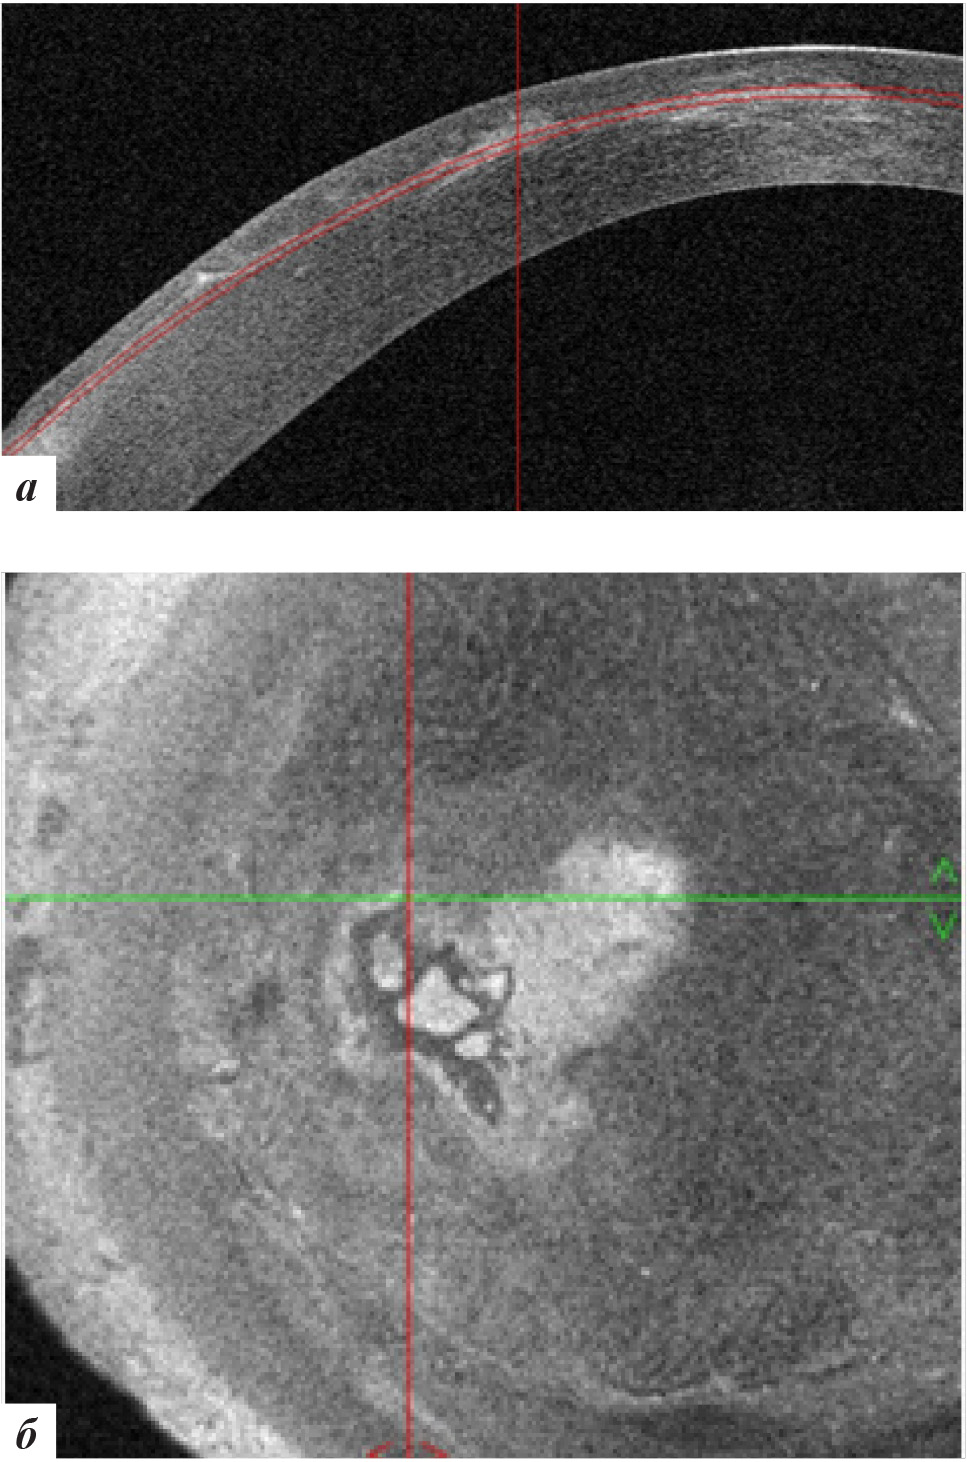

Рис. 2. Данные ОКТ роговицы правого глаза: а – горизонтальная проекция; б – фронтальная проекция

При офтальмобиомикроскопии глаз спокоен, в роговичном интерфейсе в центральной оптической зоне (ЦОЗ) и в параоптической зоне во внутреннем отделе определяется сливная зона вросшего эпителия 2 × 4 мм с зоной перифокального отека (рис. 3), что подтверждалось данными ОКТ роговицы (рис. 4). ПЭК OS: 2830 кл/мм2.

Рис. 4. Данные ОКТ роговицы левого глаза: а – горизонтальная проекция, б – фронтальная проекция